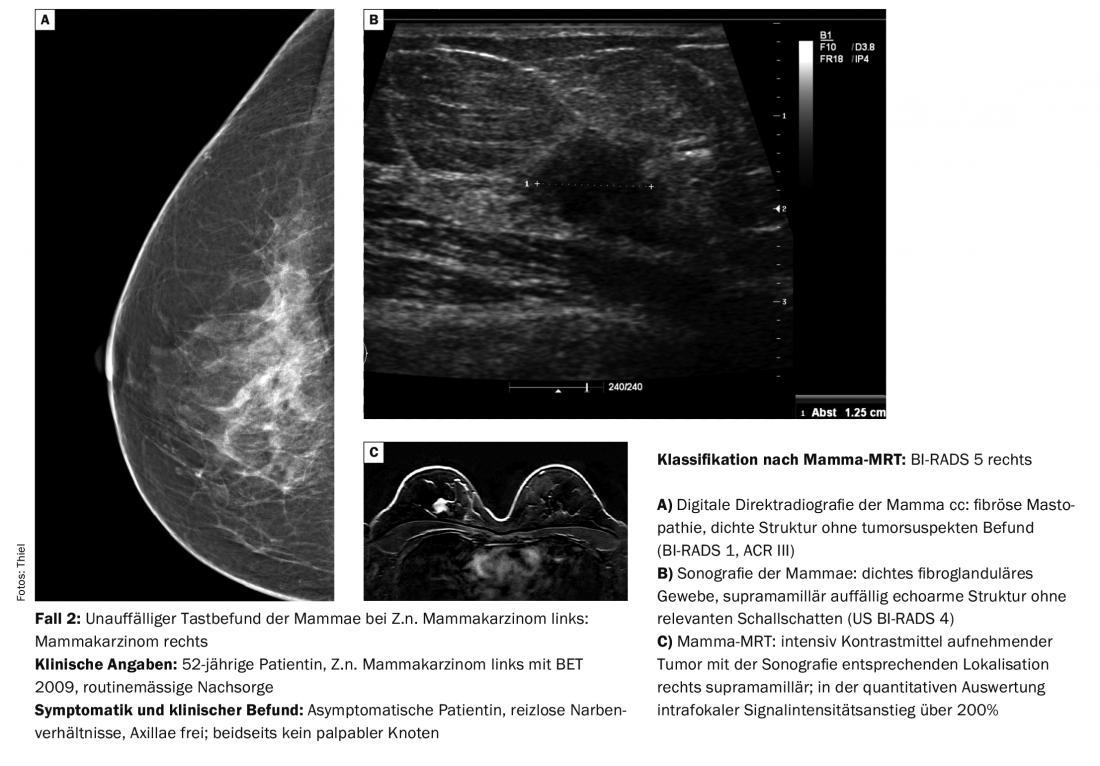

O diagnóstico diferencial dos nódulos mamários palpados corresponde em cerca de 90% a alterações benignas tais como fibroadenomas, cistos, mastopatias fibrocísticas e outras alterações mais raras. Contudo, o carcinoma é de esperar em cerca de 10% dos casos [1]. Os resultados da palpação nestes casos são geralmente nódulos grosseiros. As pequenas descobertas podem ainda ser móveis, os tumores maiores menos. Contudo, nem todas as malignidades são clinicamente evidentes (caso 2) ou, no caso de estrutura mamária densa e palpação suspeita, também podem ser claramente reconhecidas mamograficamente (caso 3).

Para além das imagens mamográficas e sonográficas, a tomossíntese digital está em vias de ser cada vez mais utilizada. Pode eliminar o mascaramento indesejável de resultados relevantes através de sobreposições estruturais e reduzir o número de resultados falsos positivos e falsos negativos da interpretação de imagens [2]. Em princípio, pode afirmar-se que a mamografia digital representa agora o padrão de diagnóstico em toda a linha e oferece vantagens consideráveis no pós-processamento (zoom, inversão, medições), para além da monitorização da visualização das imagens [3]. A RM mamária é utilizada com muito mais frequência para alterações malignas e é um instrumento fiável para diferenciar tecido cicatricial e tumores recorrentes – mesmo quando existe uma discrepância entre a clínica e a mamografia, por um lado, e a sonografia, por outro (caso 2). As indicações específicas para a utilização do método já foram descritas. No entanto, a RM ao seio é também um procedimento de diagnóstico tecnicamente muito exigente e propenso a erros; é importante evitar artefactos de movimento e erros de saturação de gordura ou tê-los em conta na avaliação [4].

Os diferentes tipos histológicos (panorâmica) de tumores limítrofes, semi-malignos e malignos nem sempre podem ser diferenciados imagem-morfológica-morfologicamente. É crucial que eles sejam reconhecidos e que o curso seja definido para procedimentos de diagnóstico ou terapêuticos posteriores, se necessário.